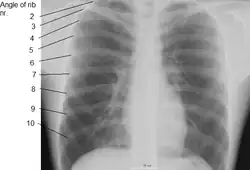

Rib cage

The first seven sets of ribs, known as "true ribs", are attached to the sternum by the costal cartilages. The first rib is unique and easier to distinguish than other ribs. It is a short, flat, C-shaped bone, and attaches to the manubrium.[6] The vertebral attachment can be found just below the neck at the first thoracic vertebra, and the majority of this bone can be found above the level of the clavicle. Ribs 2 through 7 then become longer and less curved as they progress downwards.[7] The following five sets are known as "false ribs", three of these sharing a common cartilaginous connection to the sternum, while the last two (eleventh and twelfth ribs) are termed floating ribs.[2] They are attached to the vertebrae only, and not to the sternum or cartilage coming off of the sternum.

In general, human ribs increase in length from ribs 1 through 7 and decrease in length again through rib 12. Along with this change in size, the ribs become progressively oblique (slanted) from ribs 1 through 9, then less slanted through rib 12.[7]

The ribs begin as cartilage that later ossifies – a process called endochondral ossification. Primary ossification centers are located near the angle of each rib, and ossification continues in the direction away from the head and neck. During adolescence secondary ossification centers are formed in the tubercles and heads of the ribs.[8]